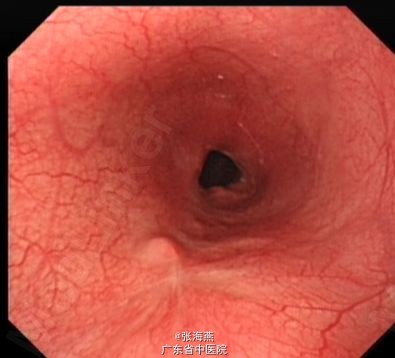

随访及讨论:患者2013年9月4日复查胃镜提示食管粘膜愈合良好,可见疤痕存在,管腔无狭窄,患者进食通畅,无不适感。对于此巨大平滑肌瘤,内镜成功切除,可避免患者开胸手术,大大提高了患者生活质量。